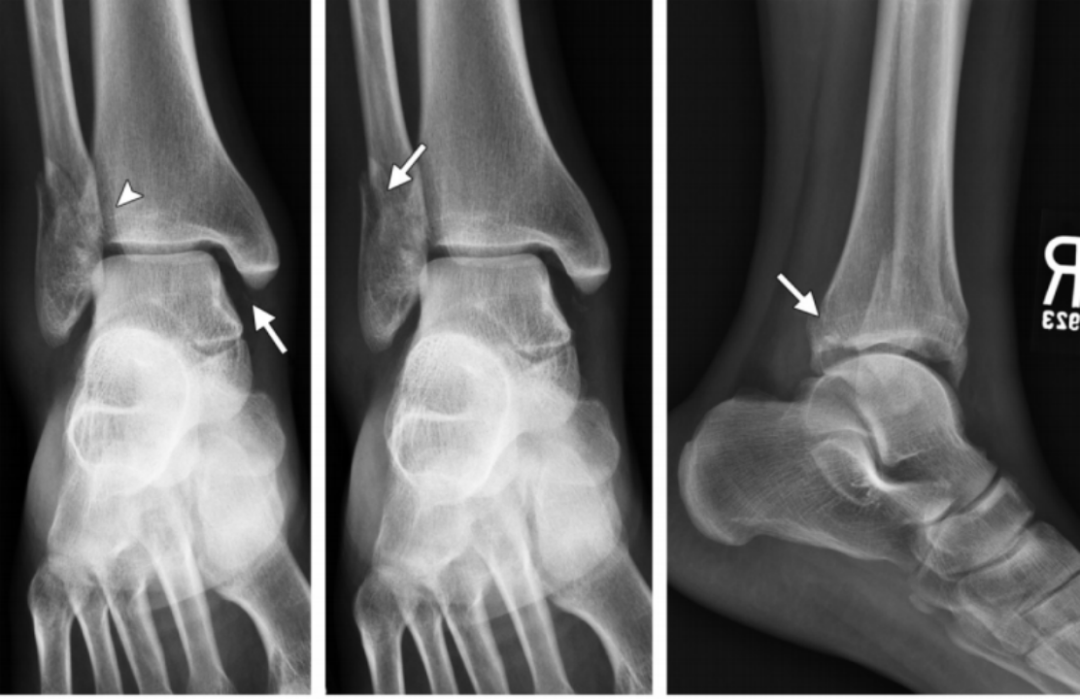

2、旋后(内翻)外旋损伤(简称 SE)

损伤时患足呈旋后位,距骨外旋,胫骨内旋,因此在损伤初期三角韧带松弛,当距骨继续外旋,腓骨受到向外后推挤,胫腓下联合前韧带及三角韧带紧张。

分为四度:

I 度:首先在外旋力作用下发生下胫腓前韧带断裂,该韧带断裂可以发生在腓骨附着点撕脱骨折(Wagstaffe 骨折)、韧带本身或者胫骨附着点撕脱骨折(Tillaux-Chaput 骨折)。

I 度损伤 X 线显示:胫腓骨间隙轻微增宽,提示下胫腓前韧带断裂;软组织肿胀;侧位片显示后踝未发生骨折。此型在 X 线上是隐匿的。

Ⅱ 度:由于距骨给腓骨施加了旋转力,导致腓骨在胫骨关节面顶部发生斜行或螺旋形骨折,骨折线一般自前下方斜向后上方。

II 度损伤 X 线片显示:胫腓骨间隙变宽,提示下胫腓前韧带断裂;腓骨螺旋形骨折;侧位片显示腓骨骨折位于下胫腓联合水平,骨折线由前下到后上,后踝无骨折。

Ⅲ 度:若外旋的力量进一步作用,可导致下胫腓后韧带断裂,或韧带在腓骨后结节附着点撕脱,或其胫骨附着点撕脱骨折(Volkmann 骨折)。

IV 度损伤 X 线片显示:胫骨腓骨间隙变宽,提示下胫腓韧带联合断裂;腓骨螺旋形骨折,腓骨骨折位于下胫腓联合水平,骨折线由前下到后上,内踝间隙增宽,提示三角韧带断裂;侧位片显示后踝无明显骨折,但下胫腓后韧带可能断裂。